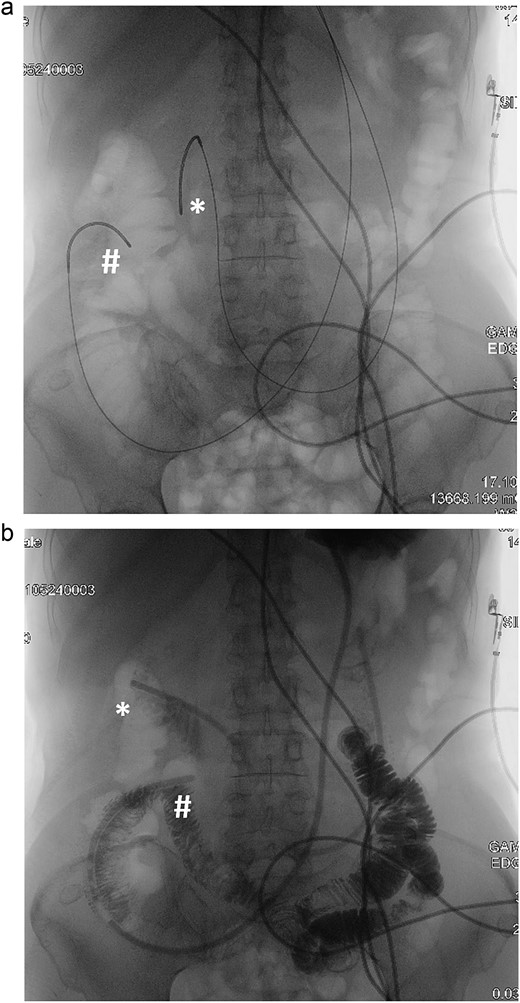

Double naso-enteric tubes was placed for stenting, enteric feeding and decompression (one was in the distal efferent limb, the other was in the proximal afferent limb). Savary-Gilliard guidewires were placed through-the-scope, across the angulated point. The endoscope was then totally withdrawn, leaving the guidewire in place. Naso-enteric tubes were threaded over the guidewire across the obstructed segment by using two 16-French single lumen plastic nasogastric tube (125 cm in length). The position of the tubes was confirmed by fluoroscopy and contrast study (Fig. 3).

Fluoroscopy and contrast study: (a) Savary-Gilliard guidewires were placed, (b) naso-enteric tubes were placed (*: afferent limb, #: efferent limb).